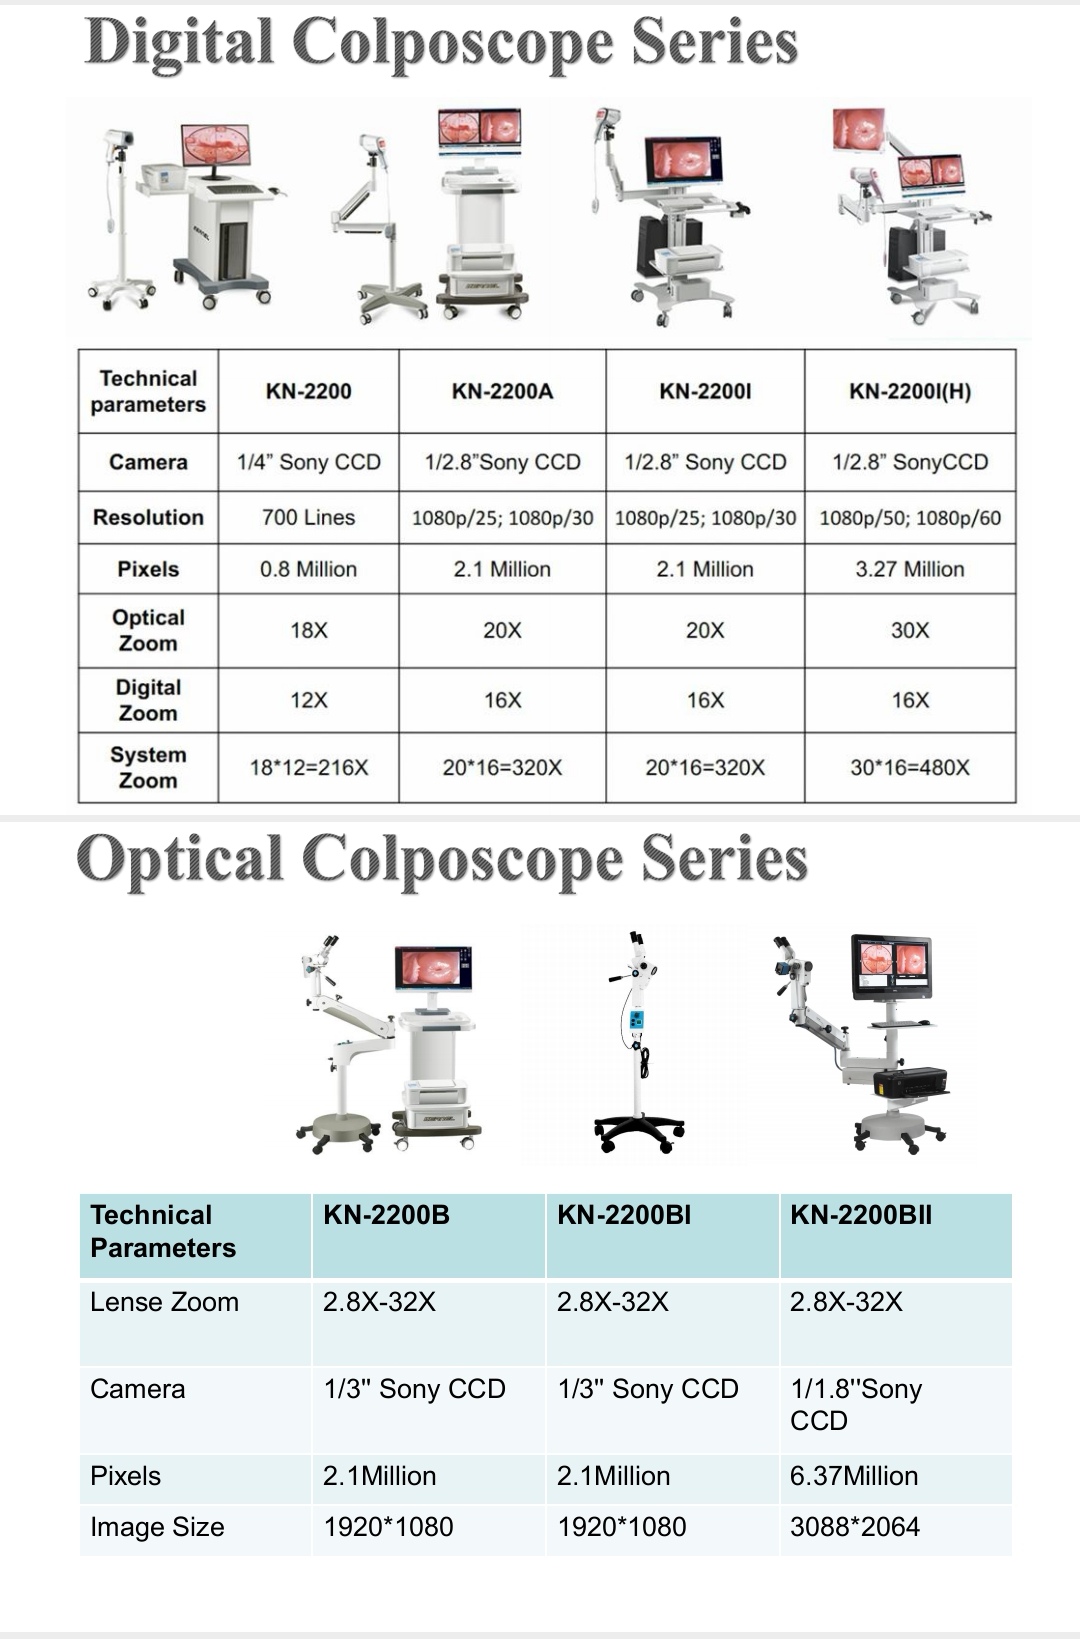

Kernel KN-2200IH cheap Electronic gynecology sony CCD video colposcope 20MG pixels trolley model

$1,690.00 - $3,430.00 / Unit

1.0 Units

Kernel KN-2200 CE ISO colposcopy colposcopio digital video camera colposcope made in China

$1,100.00 - $2,300.00 / Unit

1.0 Units

Kernel KN-2200BI manufacturer Removable Optical Colposcope for Vagina and Vulva Handheld Colposcopy Gynecology video colposcope

$2,550.00 - $3,600.00 / Unit

1.0 Units

Kernel KN-2200B CLINIC use CE optical colposcope Full hd vagina colposcope factory price colposcope

$2,750.00 - $3,670.00 / Unit

1.0 Units